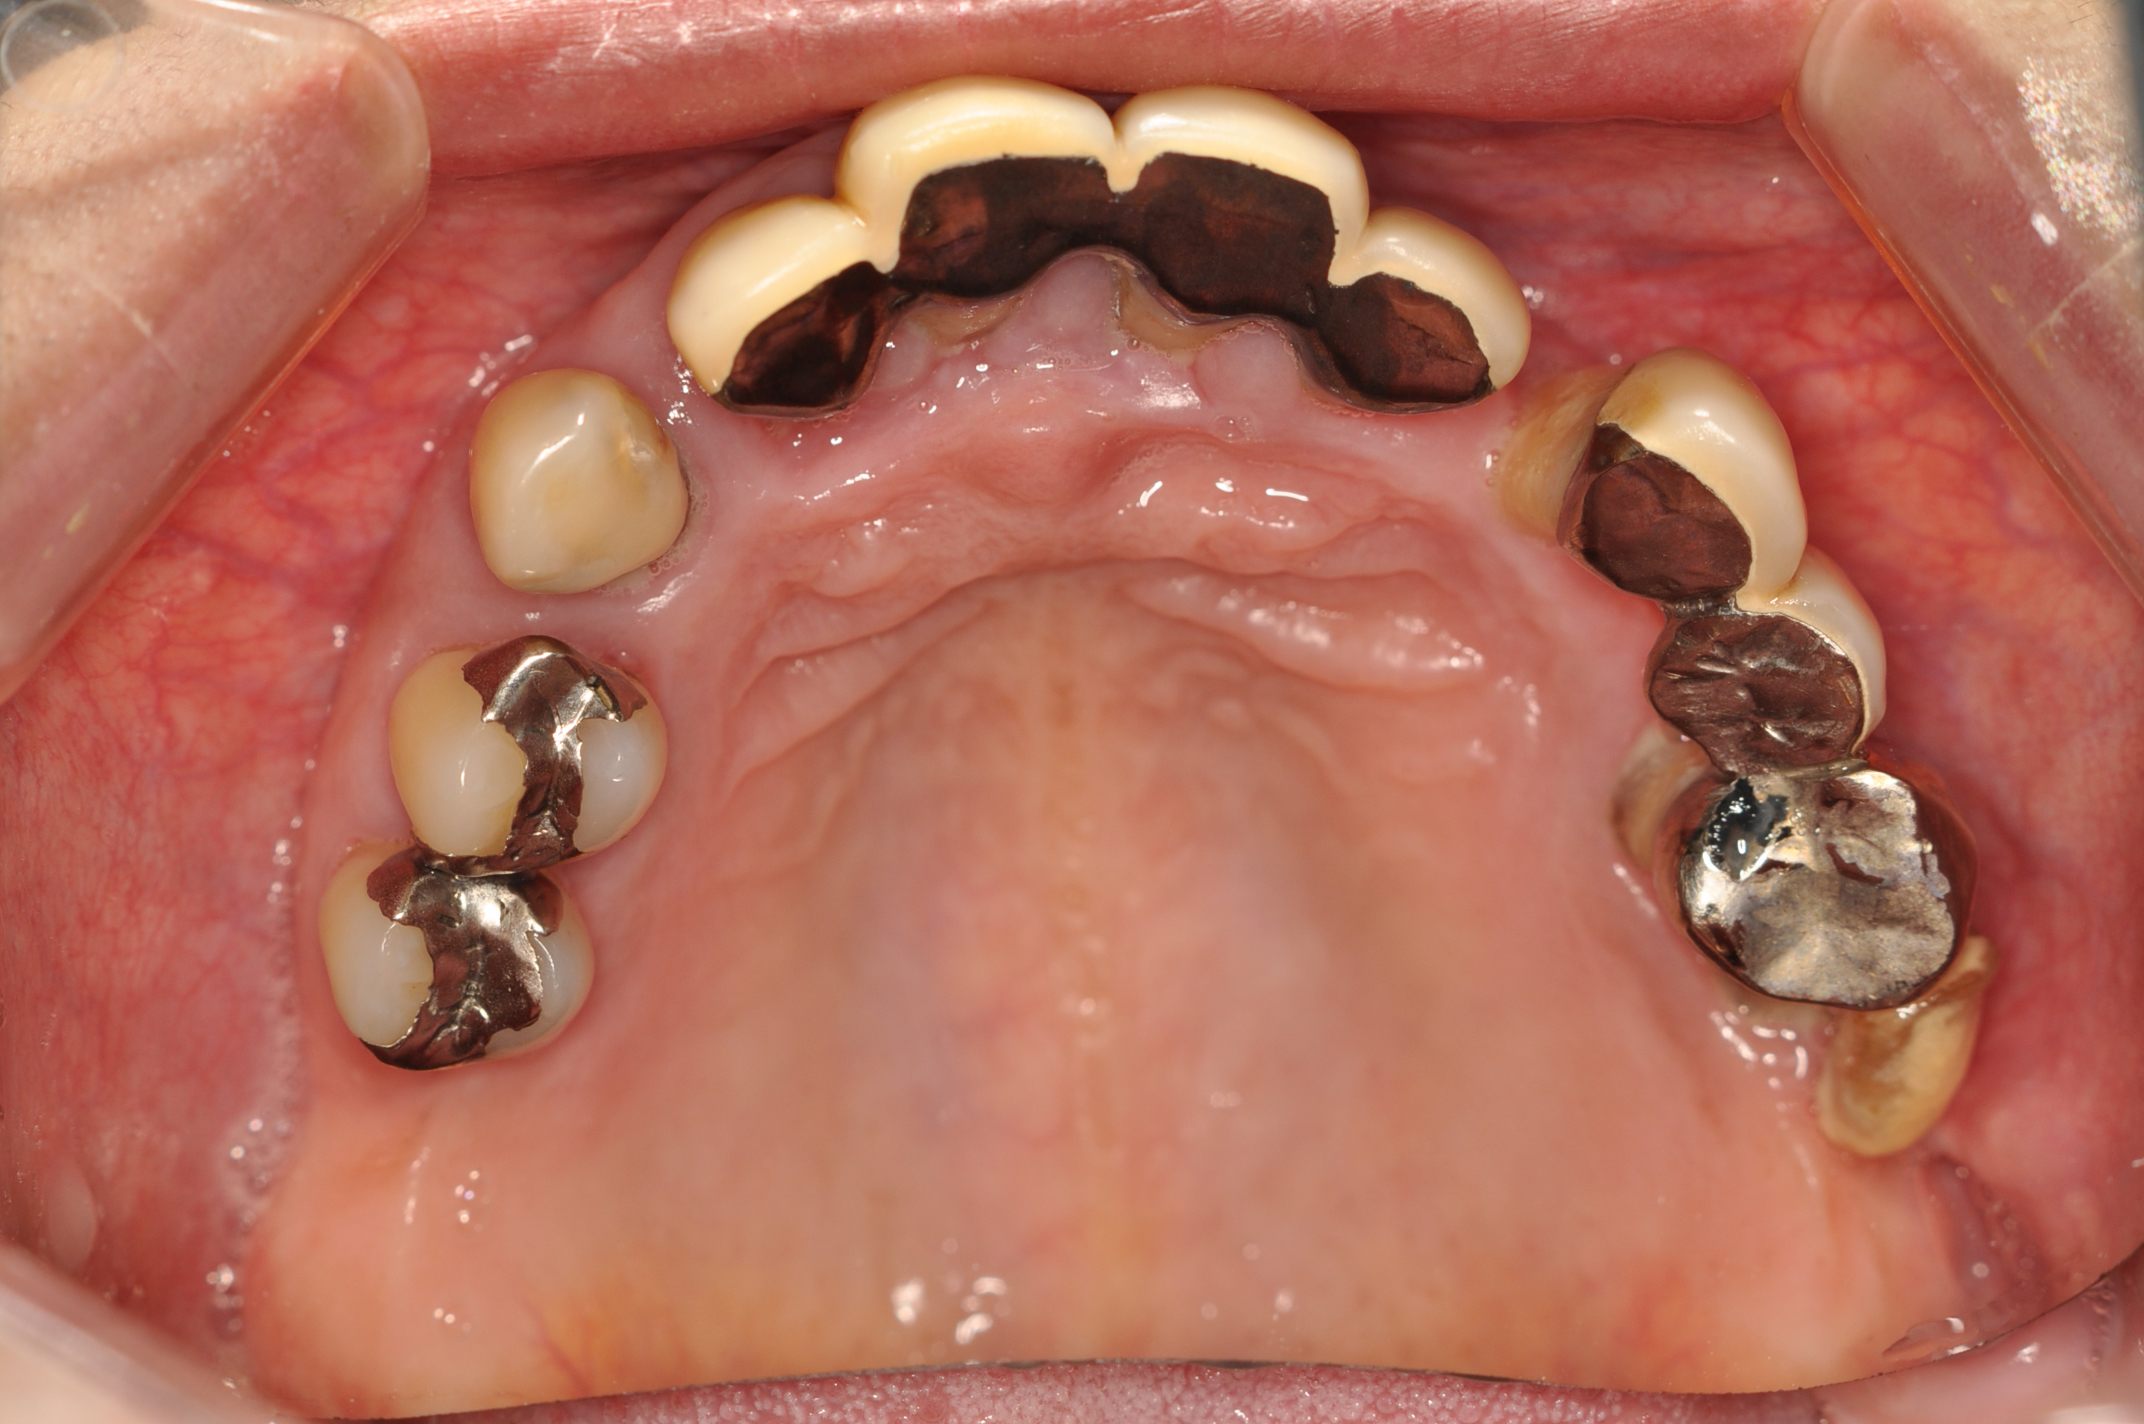

50代女性 部分義歯で対応した重度歯周病症例

娘さんがHPで安藤歯科を探していただいたそうです。義歯が入っているように見えない事が治療条件でした。

前歯をなんとかしたい

ステージIVグレードB 審美障害

治療内容

歯周基本治療

歯周外科

抜歯

補綴治療

抜歯部位

FDI表記 23 25 26 35 37 42 44 45 47